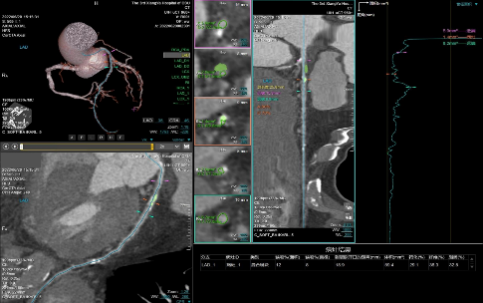

心血管成像能力方面目前

业内最好

面对高心率达到200bpm的患者,心律高度不齐、房颤、房扑的患者,都能够呈现清晰的图像质量:

(1)拥有业内最宽的16厘米探测器,轻松应对复杂心率和心律;

(2)拥有业内最全的心脏冠脉成像解决方案。

高心率+高清晰+智能分析

多维度参数评估,精准影像诊断

冠脉血管显示存在动脉伪影的,利用AI冠脉运动追焦技术进行重建数据,运动伪影校正

配置高端硬件和先进软件算法,图像性能领先。可以对软斑块成分鉴别,稳定/不稳定斑块性质鉴定,支架术后/冠脉搭桥术后复查等,640层CT均可给出清晰准确的评判。

钙化组织定量计算:按冠脉分支汇总钙点,支持钙化体积计算、钙化质量计算,Agatston积分和体积积分计算